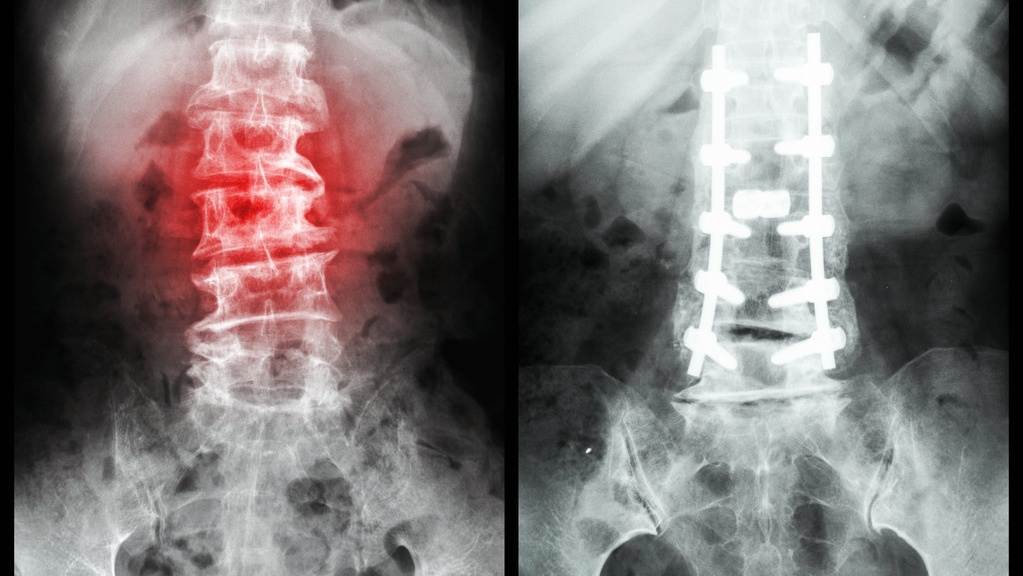

如果是出现*力暴**性骨折或者是伴有神经损伤、骨髓、有骨块突入椎管以内的骨折的话,一般是采用手术进行治疗,需要积极的进行切开、复位、内固定的手术治疗,这对于压缩性骨折的恢复有不错的促进作用。但是在手术后病人需要加以注意的一点是要卧床休息,从而对骨骼起一个保护的作用,同时还要积极地预防感染现象和防止血栓的出现。